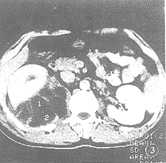

5.腎臟超音波檢查:是腎周膿腫的一種診斷性檢查方法,但CT掃描更能反映病變的全貌。CT的表現有軟組織腫塊,其中CT值下降至0~20H單位,在無造影劑增強的情況下,炎性膿腫壁CT值下降稍多;注射造影劑後,膿腫壁密度增強,周圍組織結構層次消失,病側腎臟或腰大肌擴大,腎周筋膜增厚,病灶內出現氣體或氣液平面。在CT引導下經皮穿刺可確定診斷並可查清致病菌。

鑑別點為:腎周炎性反應廣泛,常波及腰大肌,而腎結核較少波及腰大肌。右腎周膿腫。